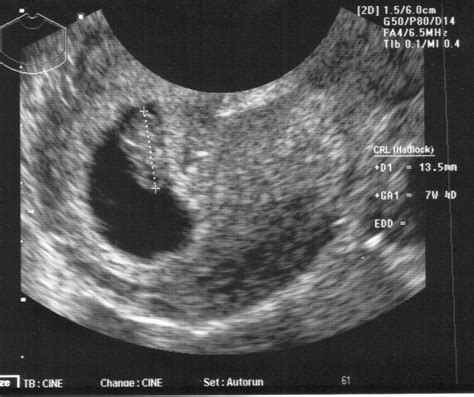

• pregnancy at week 7